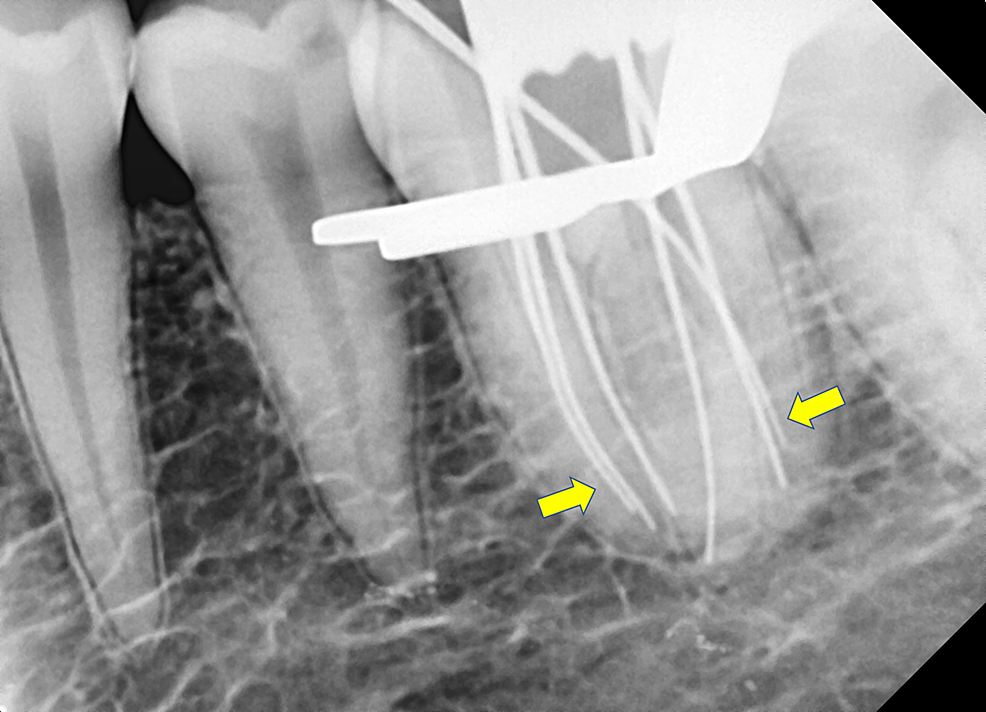

Periapical radiographs before, during,and after endodontic treatment of Root Canal Molar Radiograph A patient undergoing endodontic treatment should expect to have radiographs taken at several stages during treatment. Radiographs are important for the dentist to identify structures. The apical third of the canal system appears unusual and dilacerated. Imaging technology aids in the diagnosis of endodontic pathosis and canal morphology, assessing root and alveolar. Lie centrally within the tooth and. Pulp chamber. Root Canal Molar Radiograph.

Patient Cases Elite Endodontics Root Canal Treatment Essex Root Canal Molar Radiograph Mandibular left molar pa radiograph showing condensing osteitis in relation to both first and second molar roots. A patient undergoing endodontic treatment should expect to have radiographs taken at several stages during treatment. Pulp chamber and root canal: The apical third of the canal system appears unusual and dilacerated. The preoperative (or diagnositc) radiograph should also be used to assess. Root Canal Molar Radiograph.